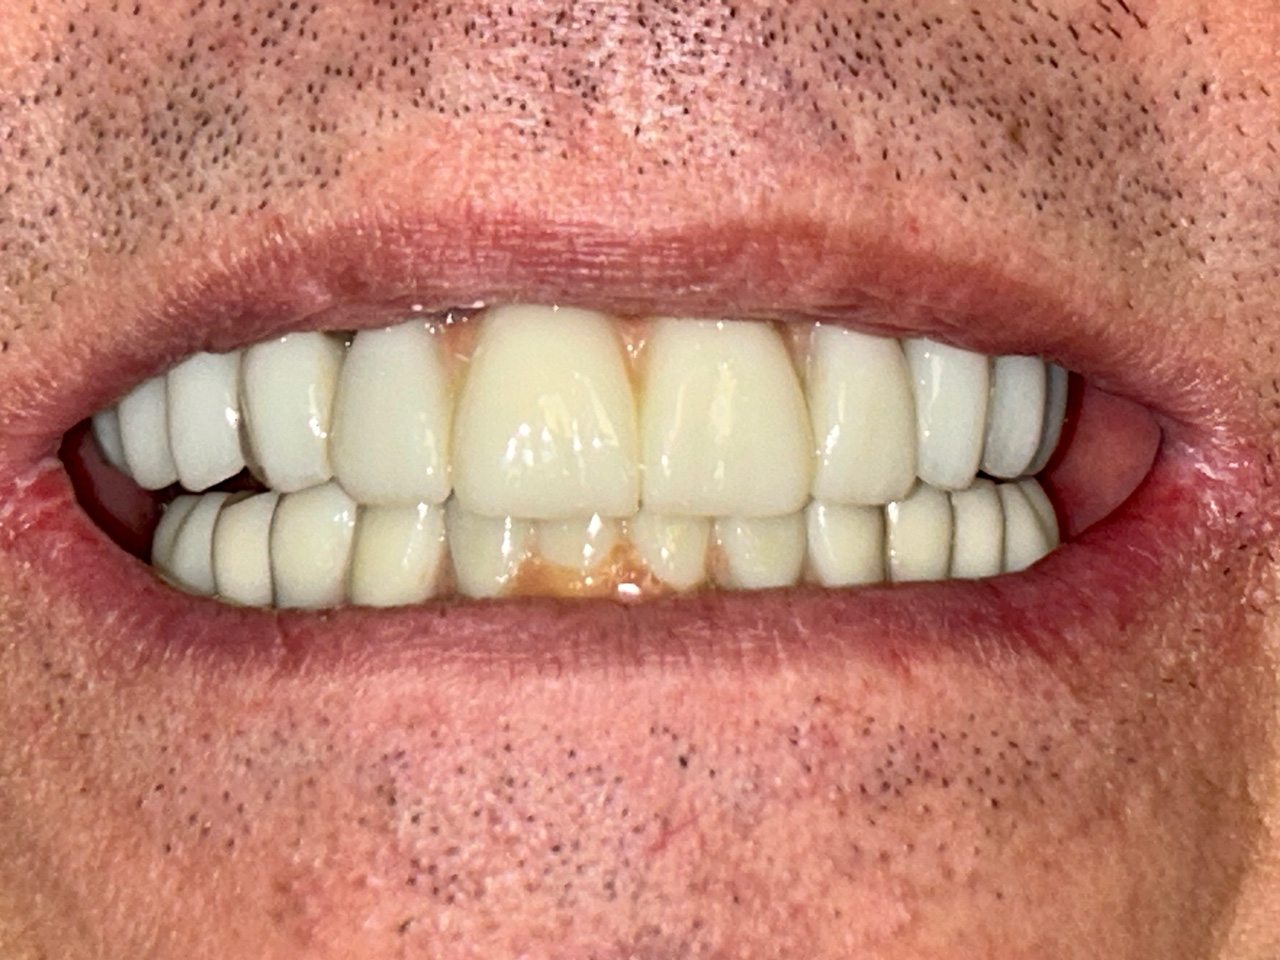

Elhanyagolt fogsor cseréje 2 nap alatt

2 nap alatt varázsoltuk ezt a szép esztétikus alsó, felső körhídat implantátumokkal megtámasztva a korábban elhanyagolt szájba. Az 1. nap 26 fogat távolítottunk el, mert annyira rossz állapotban voltak, és rögtön azonnal terhelhető IHDE svájci implantátumokat raktunk be, fentre 8, lentre 6 darabot. A sebeket összevarrtuk és intraorális szkennerrel digitális lenyomatot vettünk. 2 nap múlva pedig beragasztottuk a kész PMMA műanyag körhidakat. Dr. Kelemen Péter és a Symbion Fogtechnika munkája.